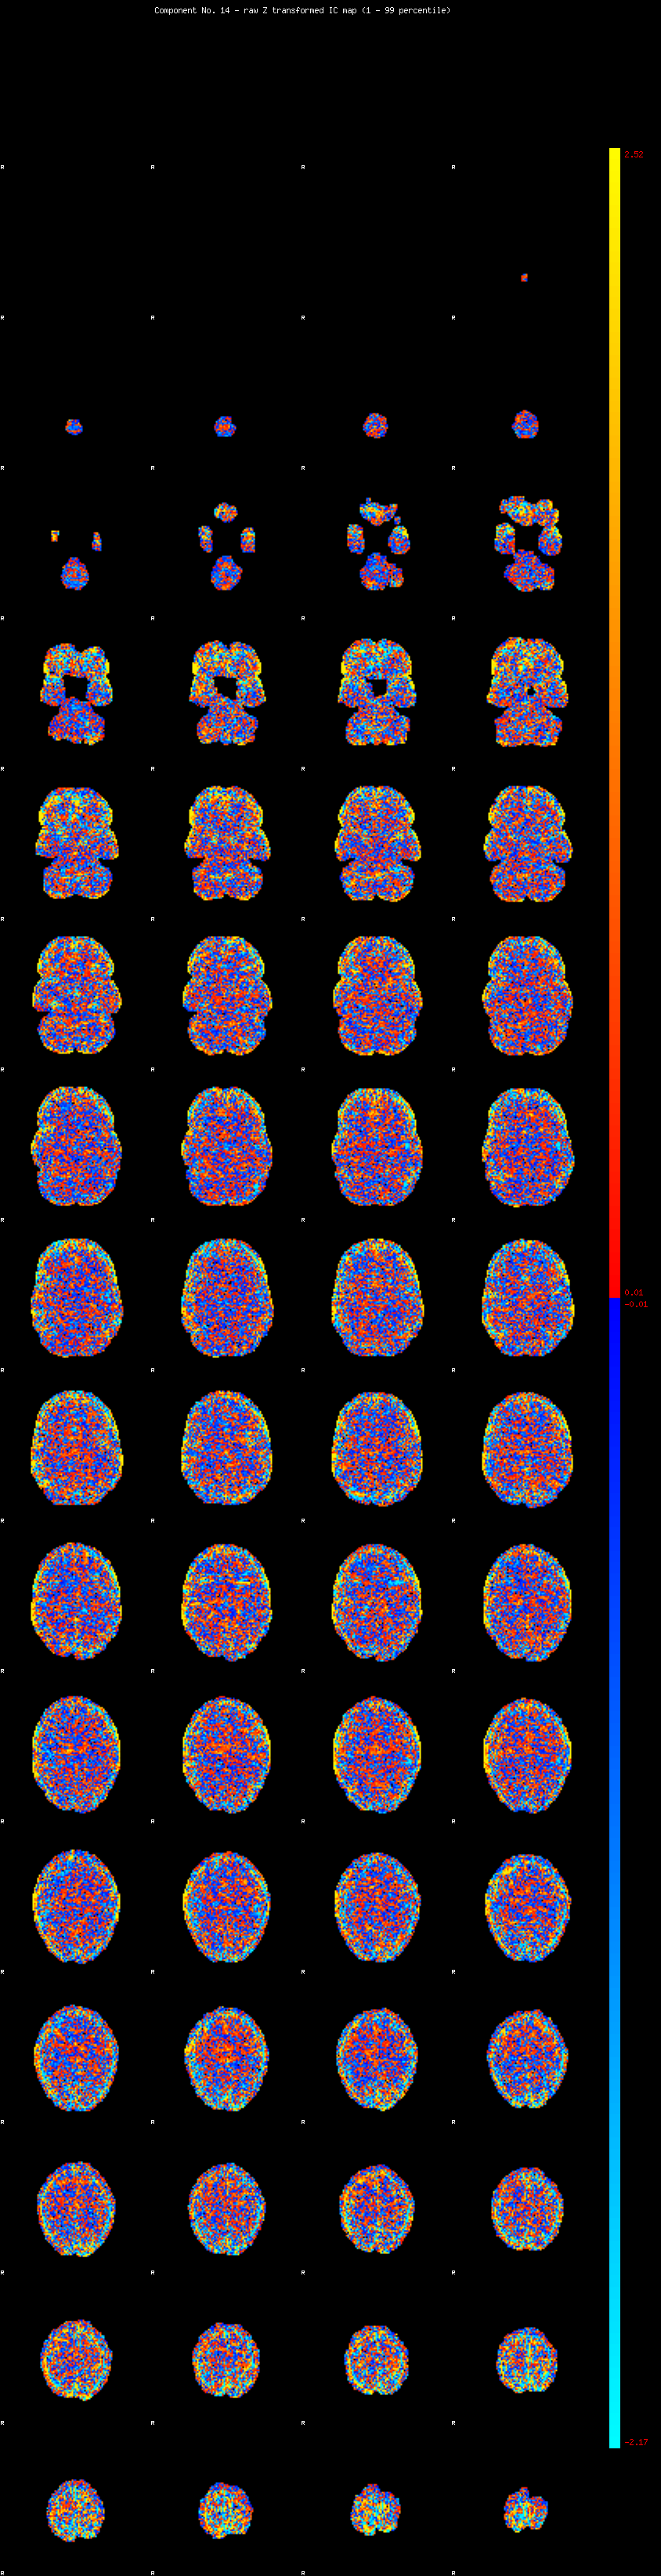

IC_14 Mixture Model fit

Means : 0.000000 3.667427 -2.853056

Vars : 1.000000 6.336244 1.668933

Prop. : 0.906222 0.053851 0.039927